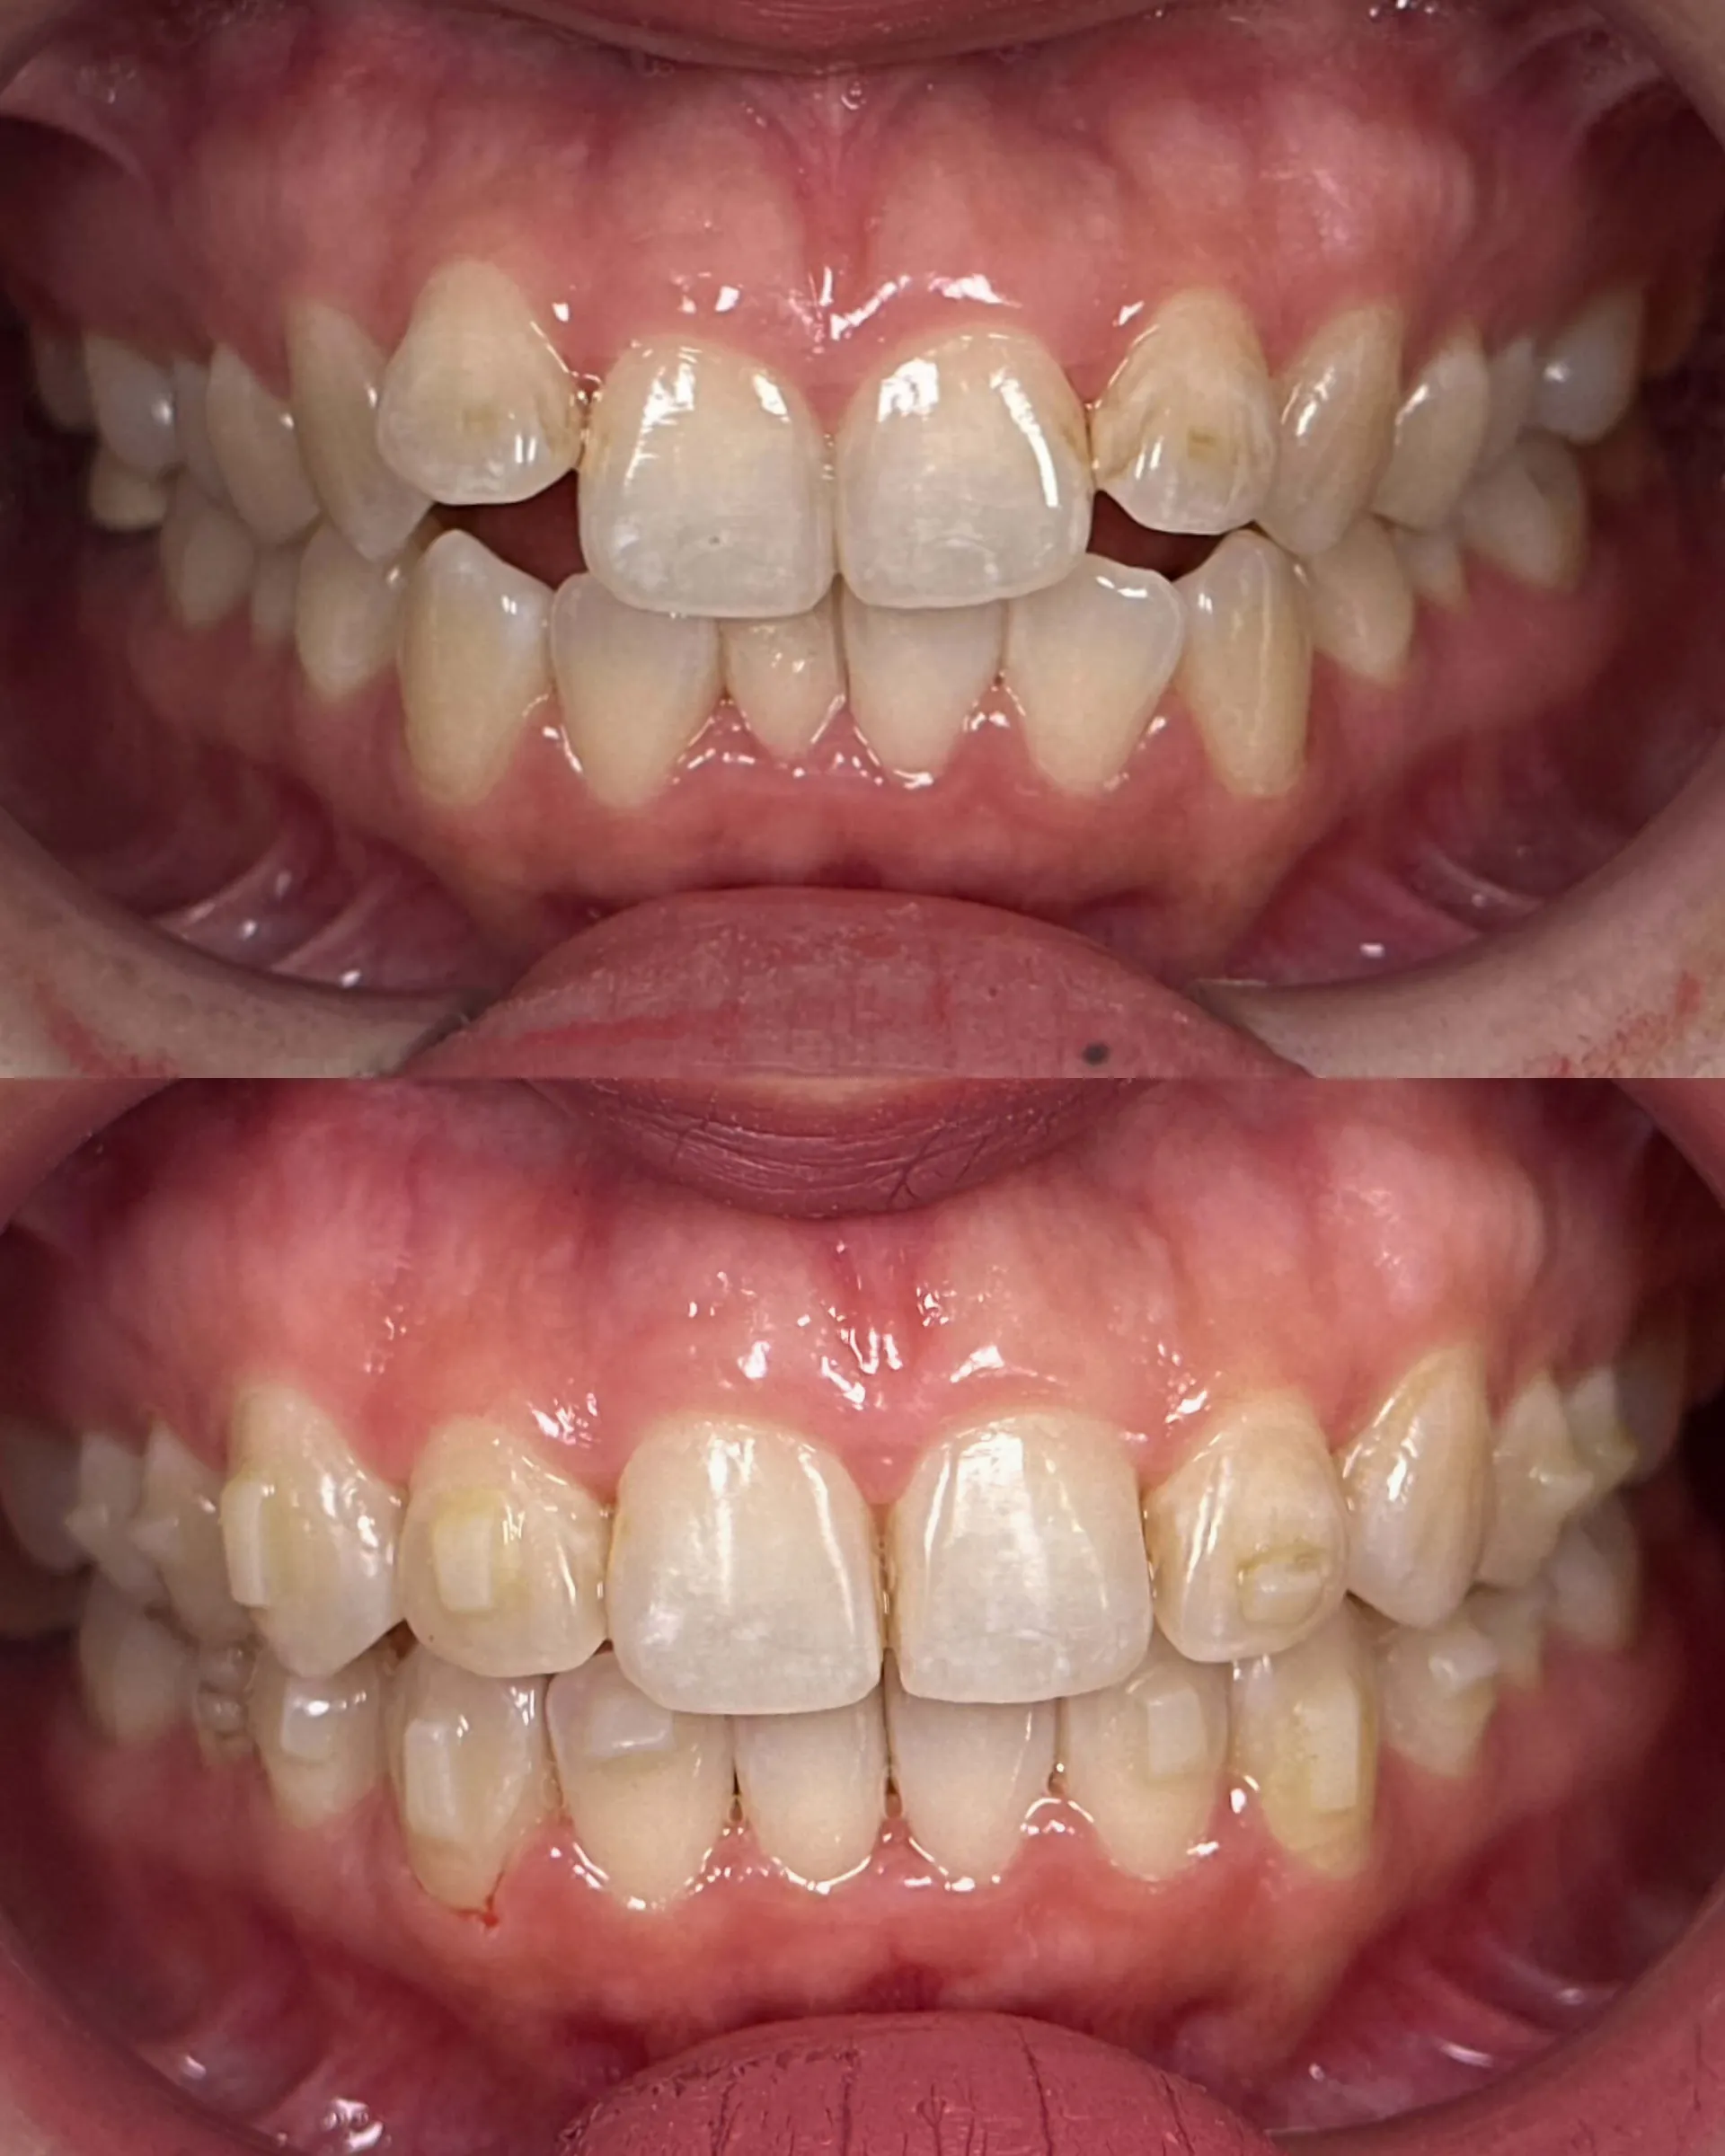

Invisalign®

As an award-winning Platinum Elite Invisalign provider, having completed over thousands of Invisalign® treatments, your smile is personally designed by our team of dentists for an aesthetically beautiful and functional end result using clear aligner technology to straighten your teeth.